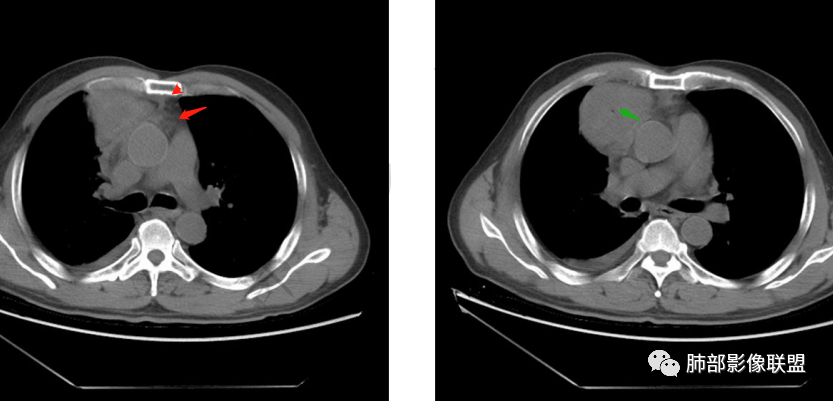

廖鹏飞:可疑胸腺动脉进入肿块

周围脂肪间隙密度增高,内部小点状很低密度影

右侧少量胸水

19日,4天后, 内部低密度影有,周围渗出增多,胸水增多

薄膜状强化

影像上周围病灶变化明显

常规肿瘤侵犯不支持,太快

应该是炎性病变渗出

脂肪密度明显,还有钙化、囊性病变,支持含脂质类病变破裂

周围是化学性炎症或出血所致

后期强化,可能与炎症有关

可能:1、肿瘤或瘤样病变破裂出血或内部物质外溢所致2、炎性病变所致

对比一下:

肿瘤样病变破裂所致纵隔炎应该没错

南边:肿瘤或肿瘤样病变破裂所致纵隔炎,这是大方向